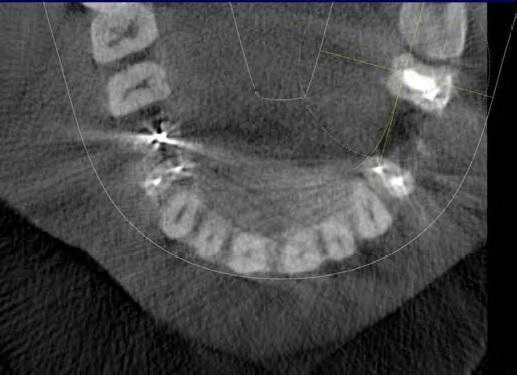

Иногда поражение проявляется клинически очевидным образом. На фото 7-10 представлен случай, когда пациент сам отметил розовую дисколорацию в пришеечном отделе правого бокового резца. Хотя чувствительность пульпы была нормальной, было обнаружено перфорирующее поражение вдоль дистально-щечной стороны зуба. Хотя предварительно считалось, что наличие розовых дисколораций свидетельствует о внутренней резорбции зуба, на самом деле в большинстве таких случаев клинически диагностируют ИПКР.

Фото 7. Случай ИПКР в области 10 зуба с формированием розовой дисколорации.

Фото 8. Подтверждение диагноза ИПКР на рентгенограмме.

Фото 9. Подтверждение диагноза на КТ-срезе.

Фото 10. Распространение ИПКТ в парапульпарном апикальном направлении (срез КЛКТ).

По причине принципов получения рентгенологических изображений, двухмерной природы рентгенограмм и значительного перекрытия нескольких анатомических образований, периапикальные снимки, или снимки по типу bitewing, часто не являются достаточно чувствительными для диагностики ИПКР. Также информативность данных методов при ИПКР часто связана с объемом потери твердых тканей зуба. Конусно-лучевая компьютерная томография (CBCT) является особенно полезной на ранних этапах регистрации очага поражения, хотя учитывая, что данный метод редко используется с целью скрининга, ИПКР снова-таки часто диагностируется как дополнительная находка при диагностике каких-то других заболеваний или при планировании комплексных алгоритмов лечения. Пародонтальная потеря костной ткани крайне редко отмечается в области внешней пришеечной резорбции.

При рентгенологической идентификации ИПКР чаще всего напоминает кариозный дефект V класса. При локализации поражений со щечной или язычной сторон из-за графического наложения на область пульпы зуба они могут вызывать некую размытость ее контура. По мере развития патологии она прогрессируют к пульповой камере, не вызывая прямого воздействия на пульпу. В большинстве случаев, даже среди обширных поражений, твердые ткани, окружающие пульпу, часто выглядят почти неповрежденными, что на рентгенограмме проявляется в форме тонкой рентгеноконтрастной линии между дефектом ИПКР и пульпой зуба.